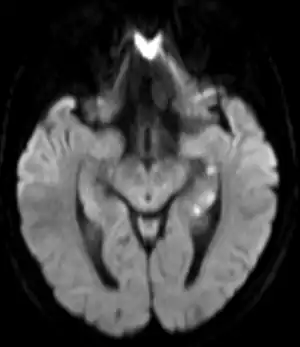

| Abnormal hippocampus findings consistent with transient global amnesia on MRI | |

Recently, moreover, both imaging and neurocognitive testing studies question whether TGA is as benign as has been thought. MRI scans of the brain in one study showed that among people who had experienced TGA, all had cavities in the hippocampus, and these cavities were far more numerous, larger, and more suggestive of pathological damage than in either healthy controls or a large control group of people with tumor or stroke.[15] Verbal and cognitive impairments have been observed days after TGA attacks, of such severity that the researchers estimated the effects would be unlikely to resolve within a short time frame.[16] A large neurocognitive study of patients more than a year after their attack has shown persistent effects consistent with amnestic mild cognitive impairment (MCI-a) in a third of the people who had experienced TGA.[37] In another study, "selective cognitive dysfunctions after the clinical recovery" were observed, suggesting a prefrontal impairment.[13] These dysfunctions may not be in memory per se but in retrieval, in which speed of access is part of the problem among people who have had TGA and experience ongoing memory problems.[12]